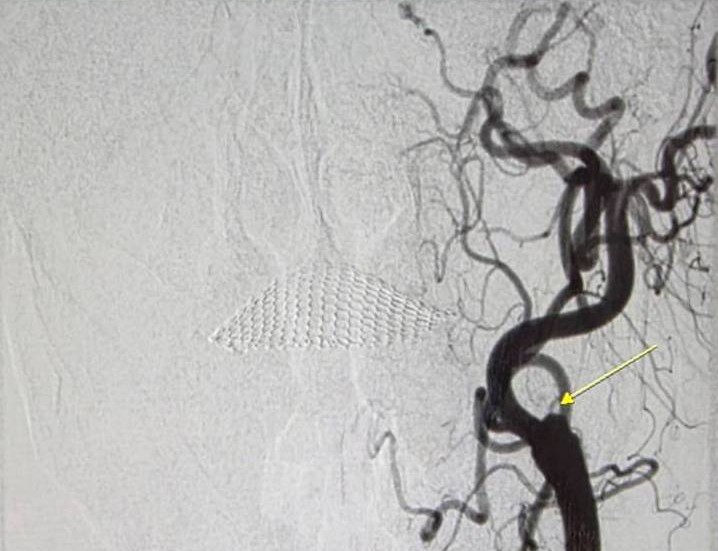

頸動脈造影顯示,左側內頸動脈血流無法通過(黃色箭頭處)。照片:大千綜合醫院提供